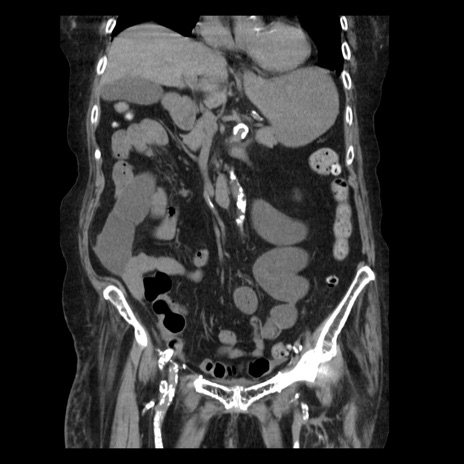

症例14(冠状断像)

【症例】 90歳代女性

【主訴】 腹痛・嘔吐

【現病歴】今朝から左側腹部痛を認めた。 経過観察していたが、嘔吐を認めたため来院。

【既往歴】 子宮癌術後

【身体所見】 意識清明、BP 127/54mmHg、P 98bpm Sp02 95%(RA)、BT 35.8°C、腹部平坦・軟腸ぜん動音聴取良好、右下腹部圧痛(+) 反跳痛なし

【データ】WBC 9800、CRP 0.46